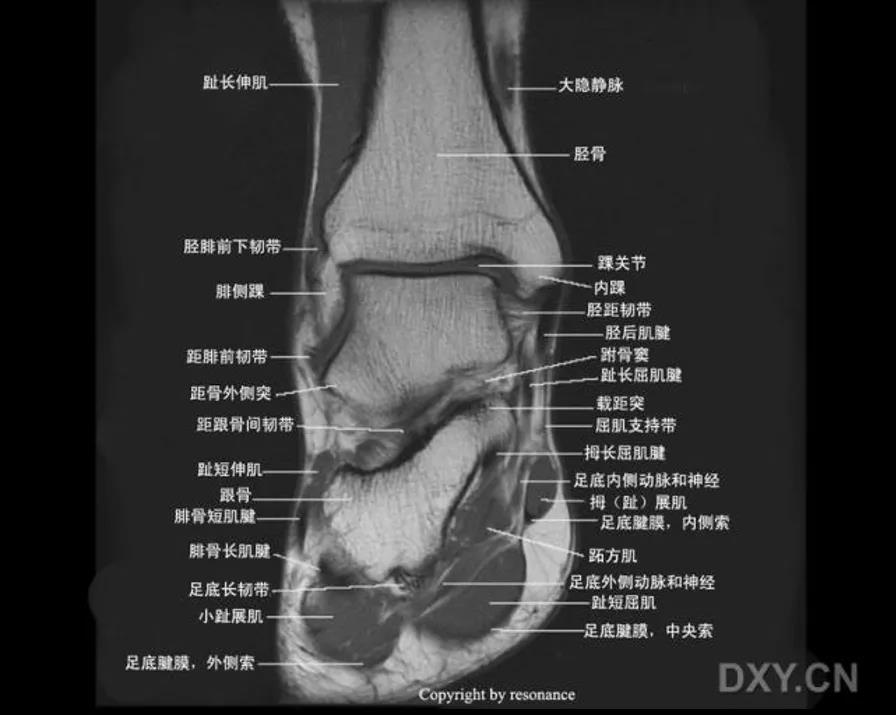

MRI:

三角韧带撕裂